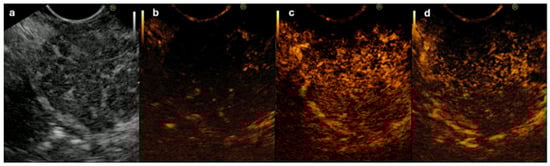

- Dietrich, C.F.; Hirche, T.O.; Ott, M.; Ignee, A. Real-time tissue elastography in the diagnosis of autoimmune pancreatitis. Endoscopy 2009, 41, 718–720. [Google Scholar] [CrossRef] [PubMed]

- Ishikawa, T.; Kawashima, H.; Ohno, E.; Tanaka, H.; Maeda, K.; Sawada, T.; Yamamura, T.; Furukawa, K.; Nakamura, M.; Miyahara, R.; et al. Usefulness of Endoscopic Ultrasound Elastography Combined With the Strain Ratio in the Estimation of Treatment Effect in Autoimmune Pancreatitis. Pancreas 2020, 49, E21–E22. [Google Scholar] [CrossRef]

- Ohno, E.; Hirooka, Y.; Kawashima, H.; Ishikawa, T.; Tanaka, H.; Sakai, D.; Ishizu, Y.; Kuzuya, T.; Nakamura, M.; Honda, T. Feasibility and usefulness of endoscopic ultrasonography-guided shear-wave measurement for assessment of autoimmune pancreatitis activity: A prospective exploratory study. J. Med. Ultrason. 2019, 46, 425–433. [Google Scholar] [CrossRef] [PubMed]

- Ohno, E.; Kawashima, H.; Ishikawa, T.; Iida, T.; Suzuki, H.; Uetsuki, K.; Yashika, J.; Yamada, K.; Yoshikawa, M.; Gibo, N.; et al. Diagnostic performance of endoscopic ultrasonography-guided elastography for solid pancreatic lesions: Shear-wave measurements versus strain elastography with histogram analysis. Dig. Endosc. 2021, 33, 629–638. [Google Scholar] [CrossRef] [PubMed]

| Elastography | Homogeneous pattern (small spotted mainly blue) spread over the pancreatic parenchyma, not just at the mass [38] | Focal heterogeneous pattern (predominantly blue with small green areas and red lines and a geographic appearance) [113] |